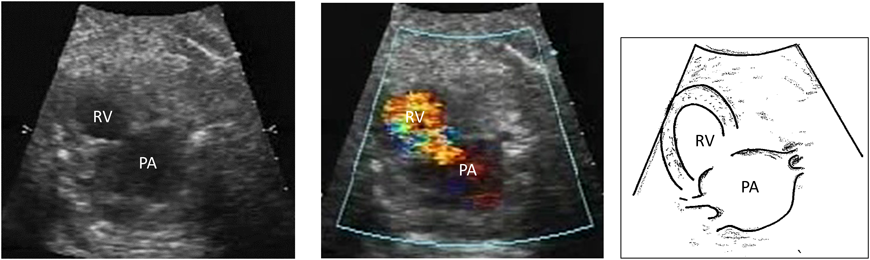

PA/IVSは肺動脈閉鎖に伴う右室低形成の程度により最終目標とする状態(Fontan循環,1.5心室修復,2心室修復)が異なるため,右心室の大きさや形態の確認を行う.三尖弁輪径と僧帽弁輪径の計測も有用である11).また類洞交通の有無と程度を確認する.類洞交通,とくに右室依存性冠血流(right ventricle dependent coronary circulation: RVDCC)の合併は出生後の予後に影響する12).(Fig. 4(video))また肺動脈閉鎖が膜様閉鎖かどうかも出生後の肺動脈弁形成術(バルーン治療もしくはBrock手術)適応に関わる.三尖弁閉鎖と同様に,卵円孔の形態や静脈管血流を確認することが生後早期BAS(balloon atrial septostomy)の必要性を評価する一助となりうる.